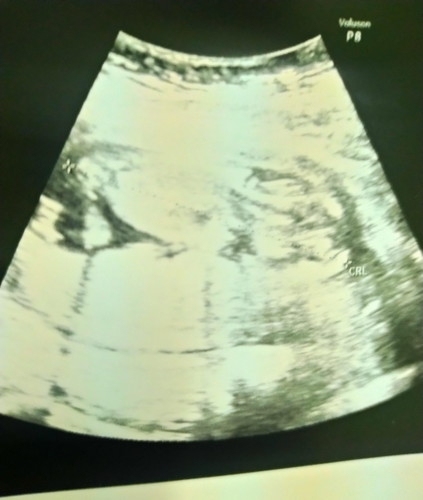

ซาวด์14วีค

น้ำตาจะไหล หมอบอกอาจจะได้ลูกสาว แต่มีลูกสาวมาแล้ว1คนอ่า ปล ดูภาพซาวด์ไม่ออกเลย